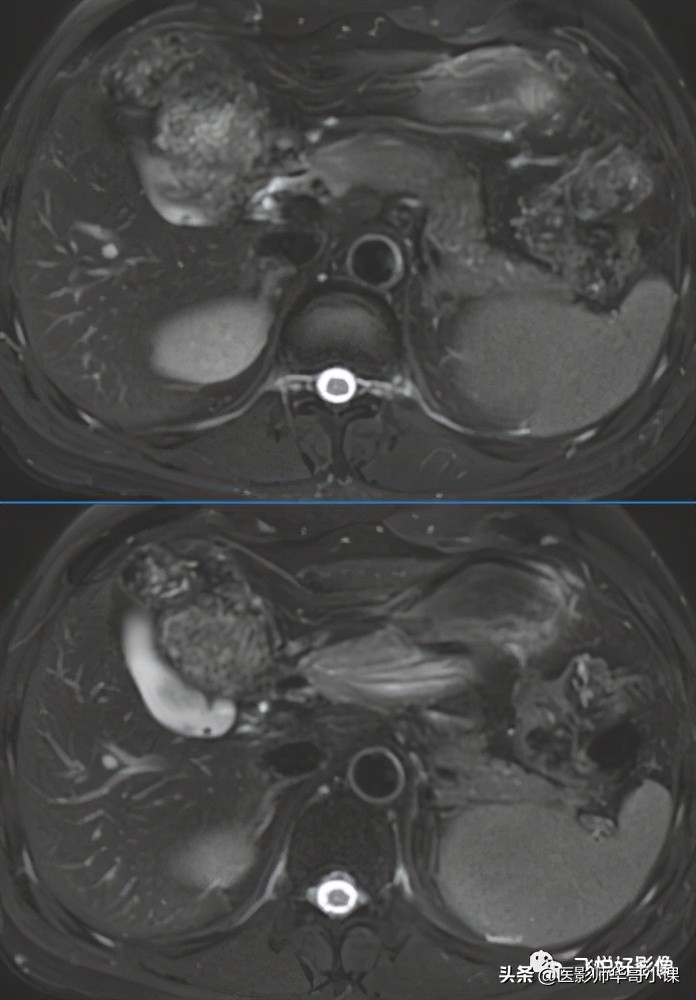

T2W示胆囊内多发结石,胆囊饱满。

T2WI_FS_TRA示:胆囊结石、胆囊壁明显增厚、胆囊窝少量积液